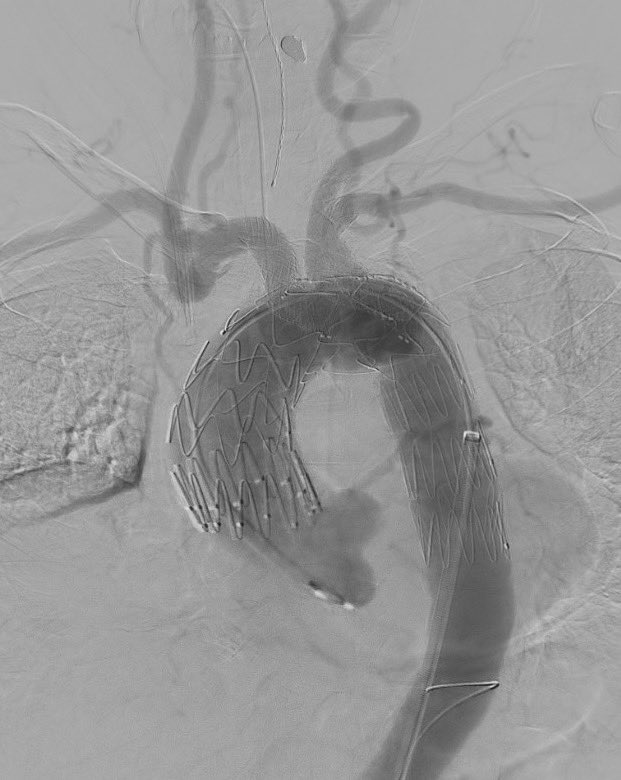

Co-Director, Aortic Center Medstar Washington Hospital Center - Georgetown University Hospital Associate Professor Georgetown Univ Uppsala University Researcher